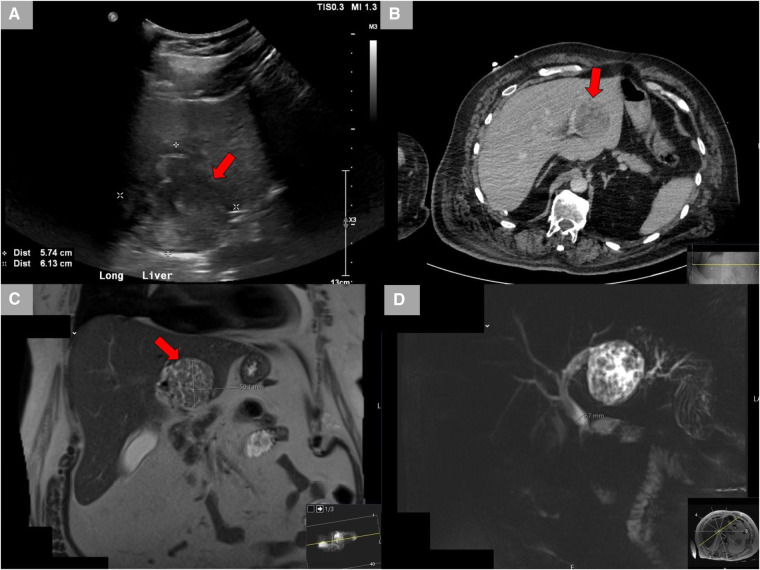

A 65-year-old male Caucasian with a history of multiple comorbid conditions presented to the emergency room with complaints of moderate constant pain at the right upper quadrant (RUQ) abdomen for the last several hours. Differential diagnoses of symptomatic cholelithiasis, cholangitis, and liver abscess were entertained. On physical examination, he was found to have normal vital signs, with icteric sclera and pain on deep palpation at the RUQ region. Upper abdominal ultrasonography (U/S) (Figure 1A) revealed a 6 cm heterogeneous mass in the left hepatic lobe and dilated gall bladder with mild sludge or stones. His laboratory results were significant for elevated liver enzymes, bilirubin and creatinine, hyperglycemia, and leukocytosis (Table 1). Subsequently, he had a hepatobiliary (HPB) iminodiacetic acid scan, which showed no excretion of hepatobiliary radionuclide related to either severe liver dysfunction or high-grade biliary obstruction. In addition, a computed tomography (CT) scan of the upper abdomen and pelvis (Figure 1B) was performed, which confirmed the U/S findings of the lesion in the left lobe of the liver and demonstrated areas of internal enhancement, and magnetic resonance cholangiopancreatography (MRCP) (Figures 1C,D) revealed mild gall bladder wall edema and a 9 mm common bile duct (CBD) dilatation of without evidence of choledocholithiasis, and it was consistent with an undetermined 5 cm mass in the left lobe of the liver. To confirm the pathology of the lesion, the referring physician performed a CT-guided biopsy, which revealed an intrahepatic papillary mucinous neoplasm. This case was discussed at the HPB multidisciplinary conference, and the patient was recommended to undergo left liver mass resection, cholecystectomy, and repair of incisional hernia. His comorbid conditions include cardiac disease, chronic obstructive pulmonary disease, diabetes mellitus, hypertension, and cerebrovascular accident. Cardiology evaluated the patient and declared him as a moderate surgical risk. He uneventfully underwent robotic left partial liver resection, cholecystectomy, lymphadenectomy, and repair of ventral hernia, and his hospital course was unremarkable. Gross pathology (Figure 2A) and histology (Figures 2B,C) revealed negative margins, and the 4.5 cm × 3.5 cm × 3.0 cm cystic structure from hepatic tissue represents the intrahepatic biliary IPMN (yellow arrow) (Figure 3) with low-grade dysplasia. The central aspect of the mass is comprised of pink-tan papillary tissue. There is no gross evidence of invasion (Figure 3). The remainder of the liver parenchyma is red-brown and firm. The patient came for regular postoperative follow-up and is still alive. The lesion had low-grade dysplasia and no malignant focus; however, the patient still underwent abdominal ultrasound after 3 months and a CT scan after 1 year. Also, he was followed up by his primary care doctor. His last visit to a hospital was on 20 March 2023 for non-IPMN or non–liver-related issues. He had a history of cerebro vascular accident (CVA) with dense right hemiparesis. His postoperative course was uneventful, other than a mild urinary tract infection for which he was prescribed antibiotics. He progressed well with physical therapy and was discharged to an inpatient rehab after 8 days of hospital stay. The patient had an extended stay at the hospital due to a lack of rehab beds. He was readmitted to the hospital from rehab due to a pulseless electrical activity (PEA) cardiac arrest for a short period, from which he successfully recovered and was discharged home with an outpatient rehab plan.